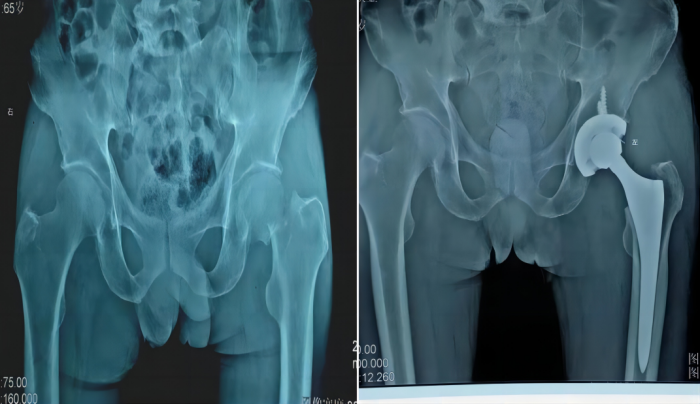

人工髋关节置换术